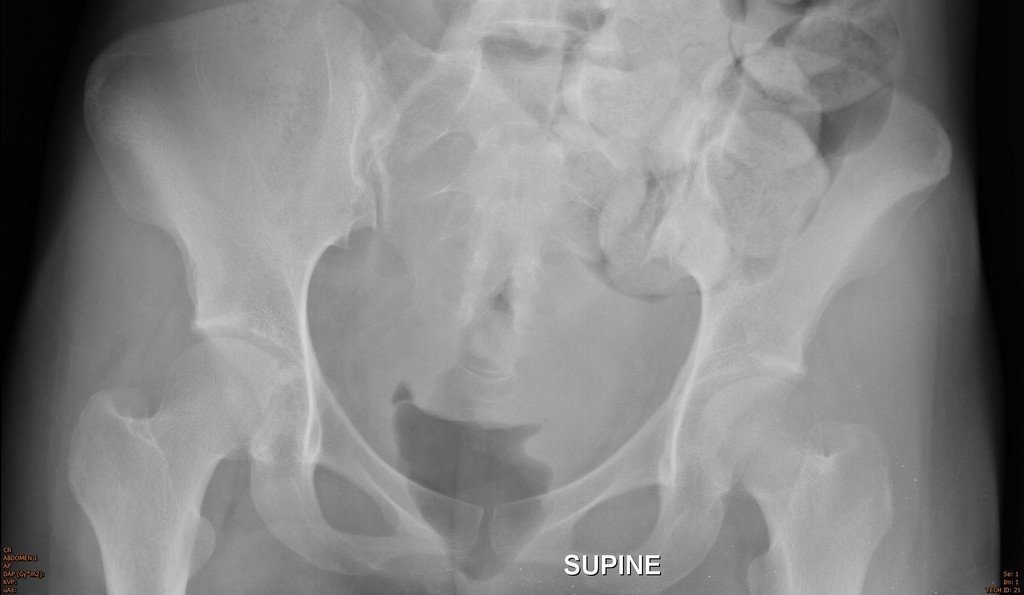

History : A 30-year-old female with weight loss and constipation

Which abnormality is not seen in this film?

A. Large bowel dilatation

B. Small bowel dilatation

C. Stomach dilatation

D. Fecal impact

Answer : C. Stomach dilatation is not seen in this film

Radiological finding :

• Colonic dilatation and fecal impaction at left side colon to the level of sigmoid colon

• Abrupt change of the colonic lumen at rectum

• Associated small bowel dilatation

Answer 1 : Large bowel obstruction

Answer 2 : Partial obstruction, because can see air in the rectum

Answer 3 : Site of obstruction : Rectum